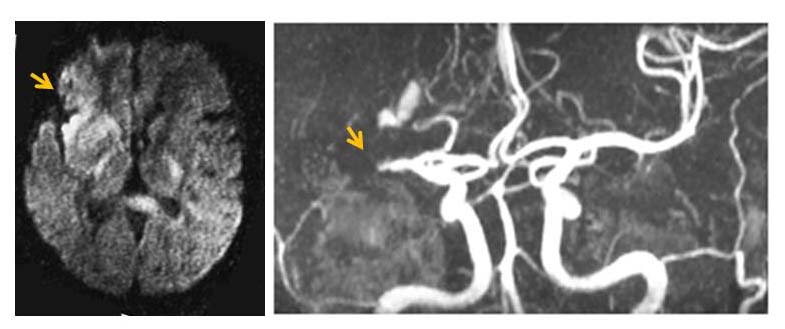

脳梗塞の治療で大切なところは,初期診断・治療と再発予防です.脳梗塞の診断には,MRIによる画像診断が重要です.拡散強調画像という急性期脳梗塞を画像上で描出できる方法が一般的となり,脳梗塞が脳のどの部位に生じているかが,比較的容易に診断するこができるようになっています.さらに,血管を造影剤などの薬剤を使用しなくても見ることのできる,MRアンギオグラフィーは,閉塞した血管を同定することが可能です.

図 左上下肢の麻痺で病院に救急車で搬送された患者さんのMRIとMRA.MRI(左)は拡散強調画像で,矢印の部分に白く移る脳梗塞が発見されました.MRA(右)では,脳梗塞の部分を栄養している中大脳動脈(↓)が閉塞していることがわかりました.